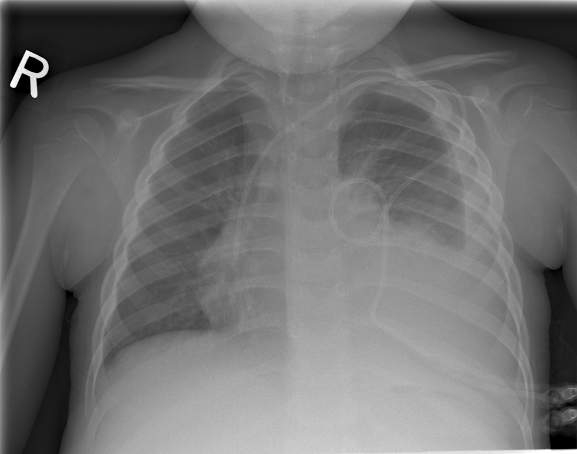

A chest X-ray with posterioanterior, lateral and left lateral decubitus views was also obtained: